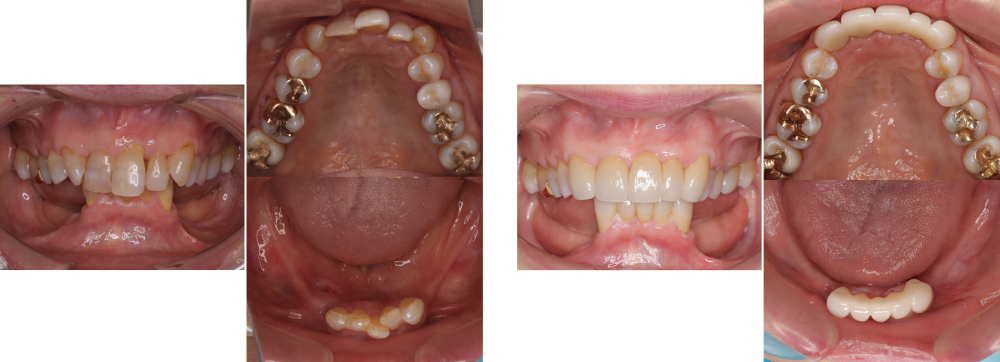

成人矯正

術前

術後

| 治療内容 | 掲載準備中 |

|---|---|

| 治療期間・回数 | 掲載準備中 |

| 費用 ※自由診療となります |

掲載準備中 |

| リスク・副作用 |

|